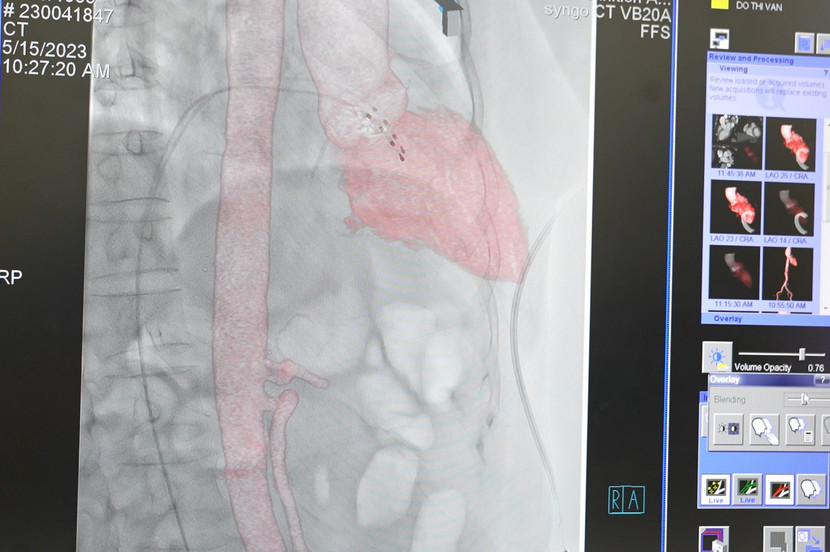

Các bác sĩ dùng một ống thông luồn từ đùi theo đường mạch máu đến van động mạch chủ bị hẹp. Dưới sự quan sát qua hệ thống robot chụp mạch tân tiến Artis pheno trong phòng can thiệp hybrid hiện đại, mạch máu sẽ hiện rõ nhờ công nghệ xóa nền, giúp bác sĩ xác định và đưa van đến vị trí chính xác. Van nhân tạo được đẩy ra khỏi ống thông bung ra và hoạt động thay thế van tim đã hỏng.

| Hệ thống chụp mạch máu xóa nền giúp các bác sĩ thực hiện can thiệp chuẩn xác |